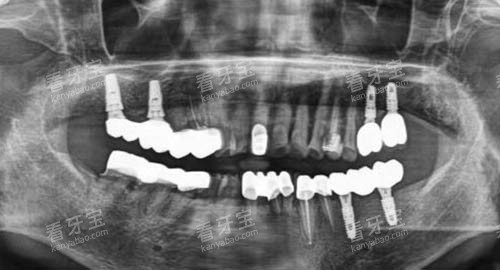

例如,智能化口腔全景机能够快速、比较准地拍摄口腔全景图像,为医生提供多方面、清晰的口腔信息,有助于更准一些诊断病情。

而种植导航系统则让种植牙手术更加更准一些、可靠,大大缩短了手术时间,减少了患者的痛苦。